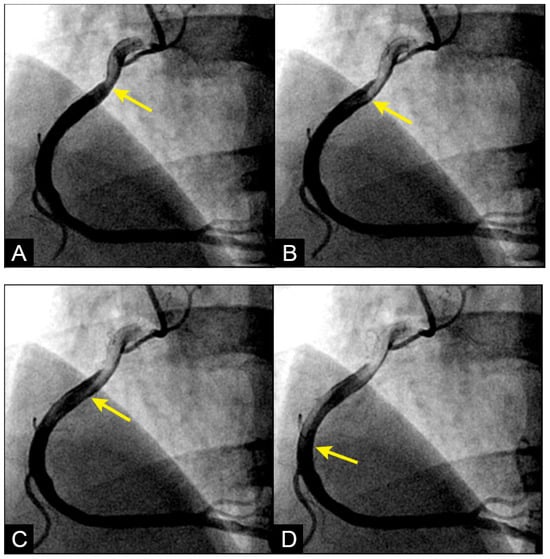

Figure 3. (AD) Laminar flow. These four coronary images are of consecutive sequence. (A) This is the angiogram of the right coronary artery (RCA), which is filled with contrast in black. (B) The blood (in white) is seen well organized with sharp border and a pointed tip, typical for laminar flow, moving in (yellow arrow). (C,D) The blood is seen following the apex of the curves (yellow arrow). This is the laminar flow following the curves in a helical fashion.